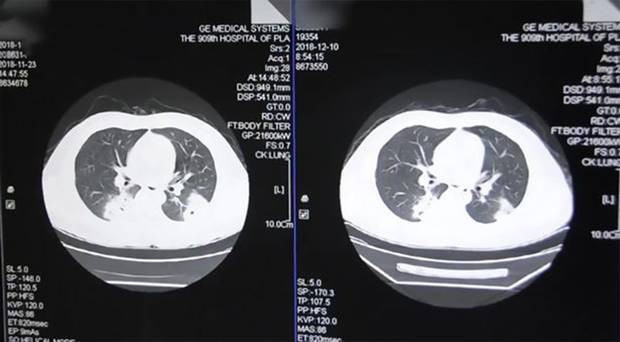

Fujian Eyaletinde yaşayan , 37 yaşındaki hasta, göğüs ağrıları ve öksürükşikayeti ile hastaneye yatırıldı. Doktorlar ayakta olan bir cins mantarın ciğerde yaşadığını fak edince şok oldular.

Çekilen röntgen görüntülerinde de açıkça görülen mantarın nedeni zayıf bağışıklık sistemi ve sürekli koklanan kirli çoraplar olarak gösterildi.